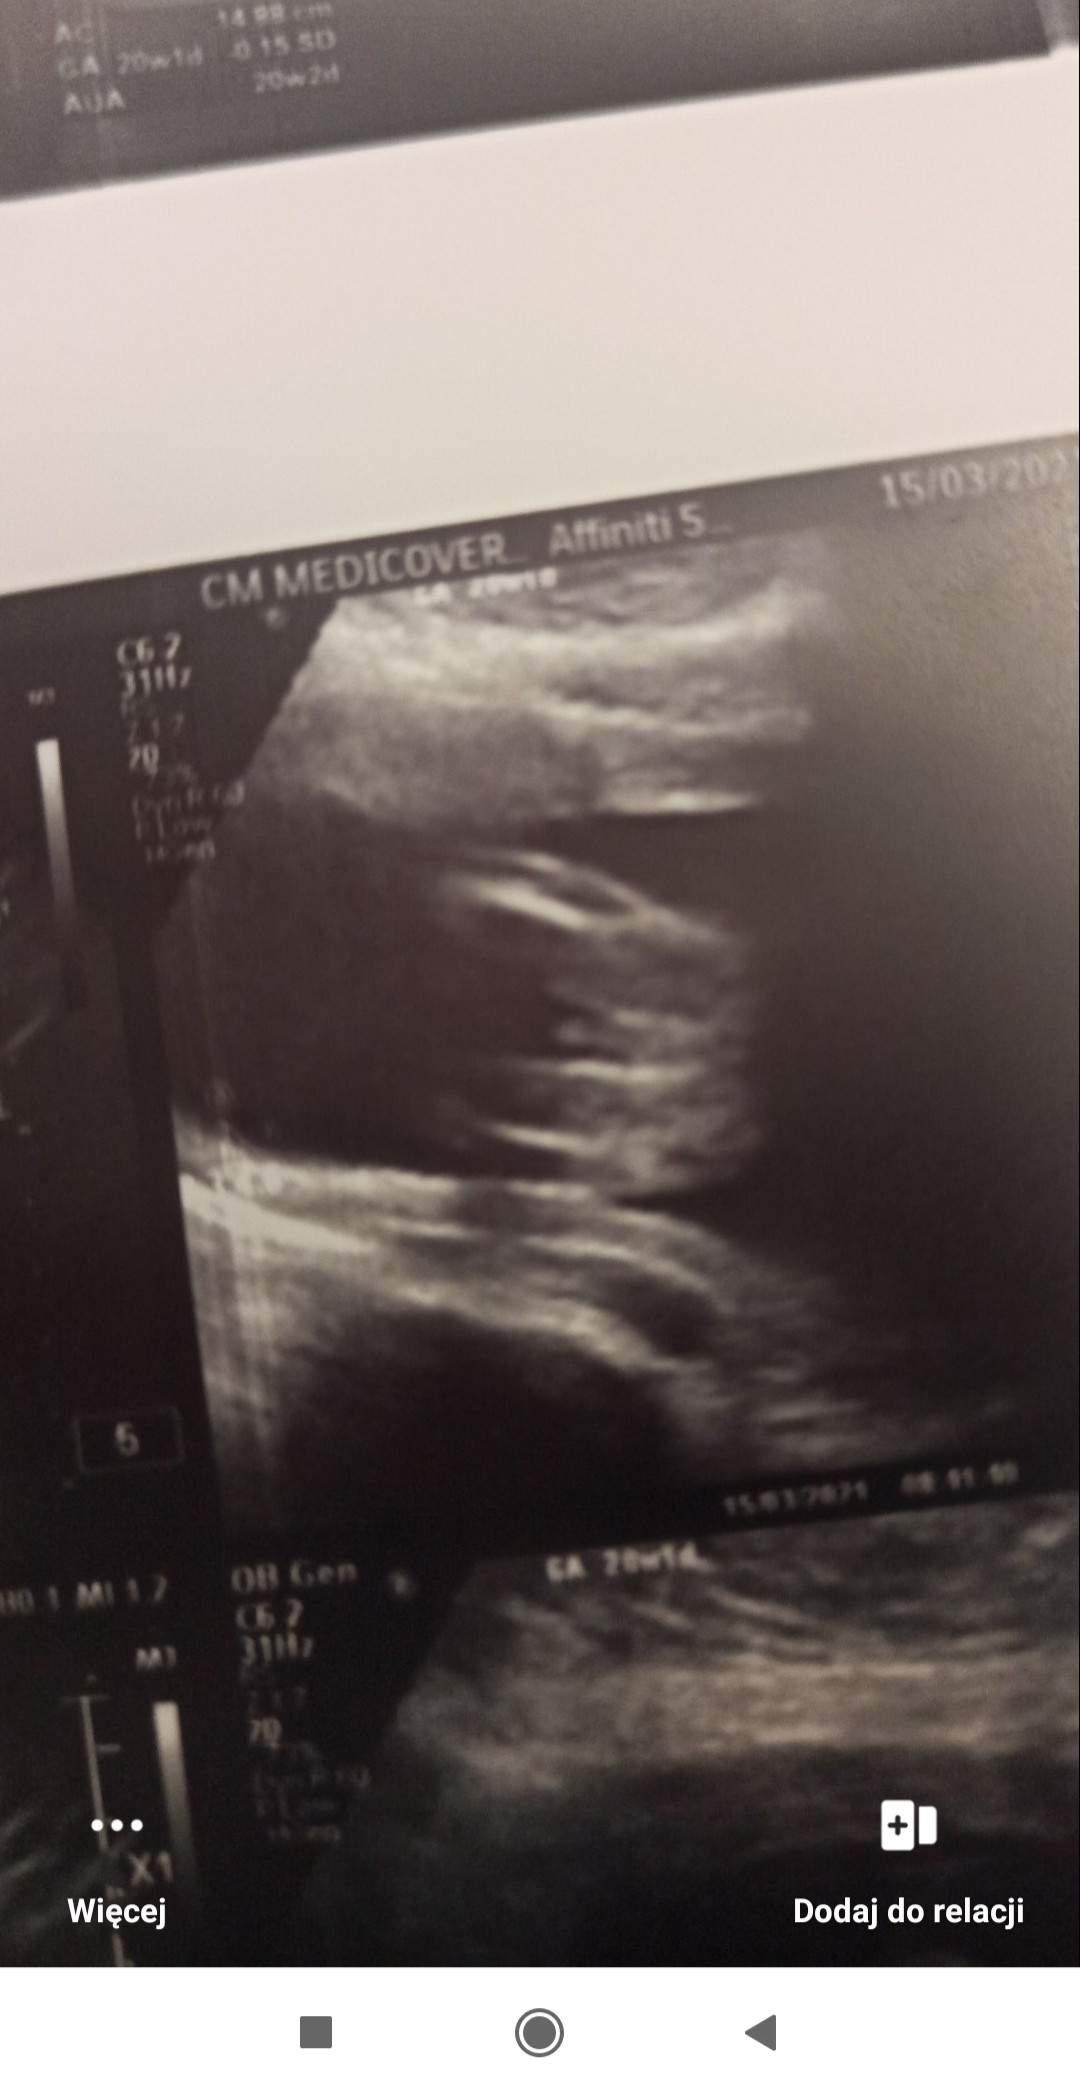

Witam w 19 tygodniu ciąży dowiedziałam się ze będę miała dziewczynkę w 20 tyg okazało się jednak , że to chłopak. Sama już nie wiem bo na jednym usg widać na pewno dziewuche a na drugim chłopca. Może to pempowina ?? Może ktoś mi pomoże rozwiązać ta zagadkę